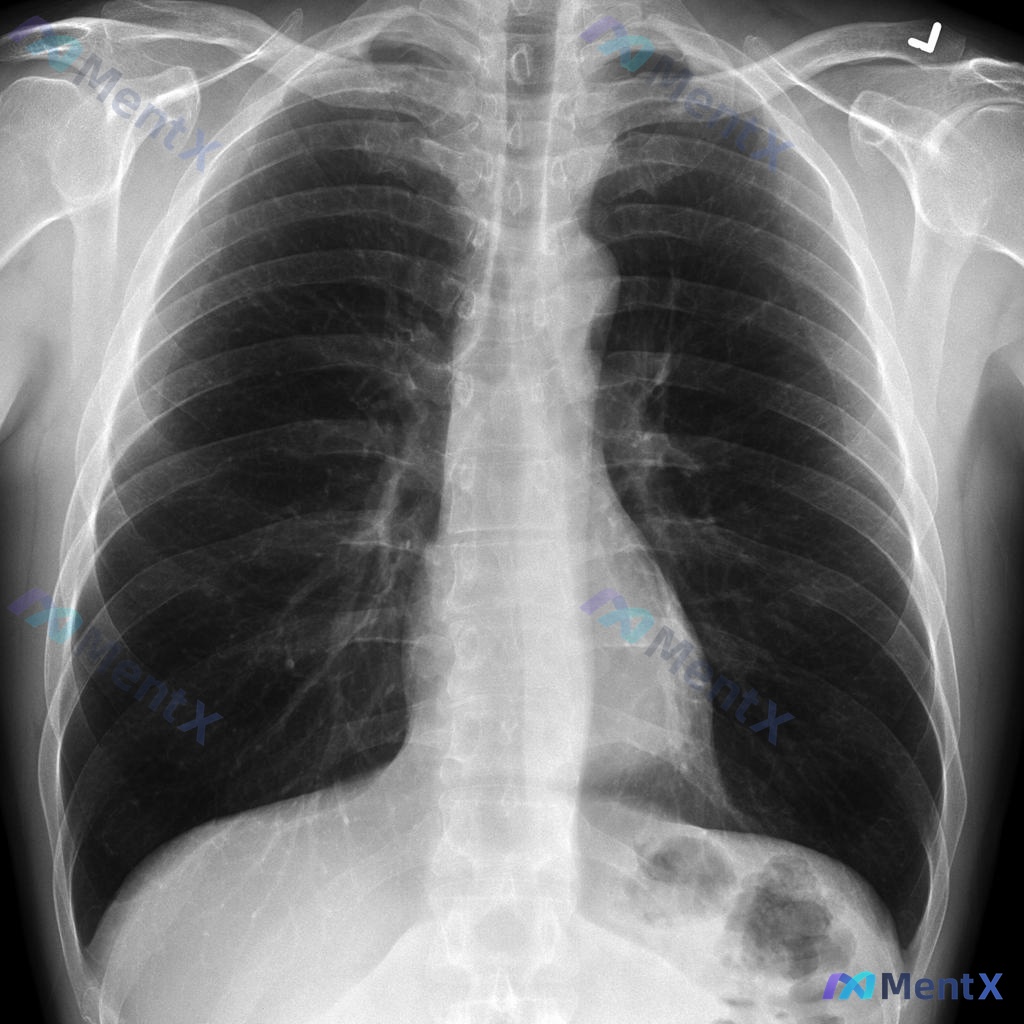

左侧肺尖薄壁含气囊腔,大家看看最可能是什么?

最近看到一份胸部CT纵隔窗图像,整理了一下分析思路,和大家讨论。 病例信息 - 扫描层面:胸廓入口水平,纵隔窗横断面 - 异常发现:左侧肺尖可见一个圆形含气空腔,边缘清晰,壁薄且均匀;右侧肺尖正常 - 其他结构:气管居中,管腔形态规则;周围脂肪间隙、大血管显示尚可;未见纵隔肿块或淋巴结肿大;胸椎、肋...